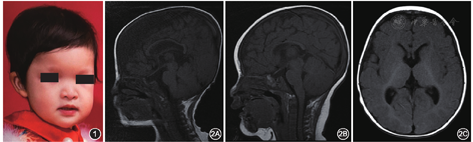

入院体格检查:体温37.6 ℃,身高64 cm,体重7.5 kg,呼吸平稳,反应迟钝,腹部无明显腹胀,可见腹腔镜手术瘢痕;面容特殊,主要表现为眼距宽、眼眶深陷、低鼻梁、鹰钩鼻、小下颌(图1);无法抬头,无法独自翻身,不能独坐。

辅助检查:头颅磁共振成像(magnetic resonance imaging,MRI)结果显示胼胝体发育不良、白质髓鞘化延迟,侧脑室旁白质容积减少(图2)。

MWS是一种由ZEB2基因变异引起的罕见的常染色体显性遗传病,全球已报道了300多例[1],包含本例中国内地共报道2例[2]。国际上尚无具体诊断标准,导致临床诊断困难。本病临床表现多样,且与多种综合征存在交叉表型,MWS独特面容是识别本病最可靠的临床特征。300多例MWS患儿均表现面容特殊,最常见为小头畸形,其余有耳垂隆起、圆形鼻尖、鼻小柱突出、前额突出、眼眶深陷、眼距增宽、宽鼻梁、鹰钩鼻、小下颌;尽管大多数患儿的特殊面容在新生儿时期就已比较明显,但仍有部分患儿的面部特征随年龄增加而逐渐变化而显现出来[3];另外所有患儿均发现智力低下(轻重程度不一);常见的其他临床表现还有:癫痫发作、尿道下裂、先天性心脏病、身材矮小、先天性巨结肠、生殖器官畸形、便秘、先天性肾脏畸形等[1]。96%的MWS患儿可在MRI检查时发现异常,其中胼胝体发育不全最为常见,其他常见异常有海马异常,侧脑室扩大和白质异常(厚度减少、局部信号改变),另有脑室颞角增大、皮质畸形、后颅窝畸形、基底神经节变大及脑肿瘤等也可见于MWS患儿[4]。中国内地发现的2例MWS患儿均有明显的面容异常及合并HSCR。本例患儿MRI结果显示胼胝体发育不良、白质髓鞘化延迟、侧脑室旁白质容积减少。第1例中国内地患儿因严重的先天性心脏病,在做MRI检查之前死于严重心衰。智力低下、小头畸形及特殊面部特征等表现在MWS患儿尤其是新生儿期常不明显,但MRI多可见胼胝体发育障碍。MWS患儿面部特征随年龄增加逐步显现,但幼儿期依然可寻见端倪,需临床首诊医生在进行体格检查时细致观察。虽然MWS合并HSCR者在既往报道中只占44.2%[1],但中国内地的2例MWS患儿均合并有HSCR。因此,若患儿诊断为HSCR且面部异常同时合并智力发育异常时,临床医生应给予高度怀疑,可考虑行MRI检查。